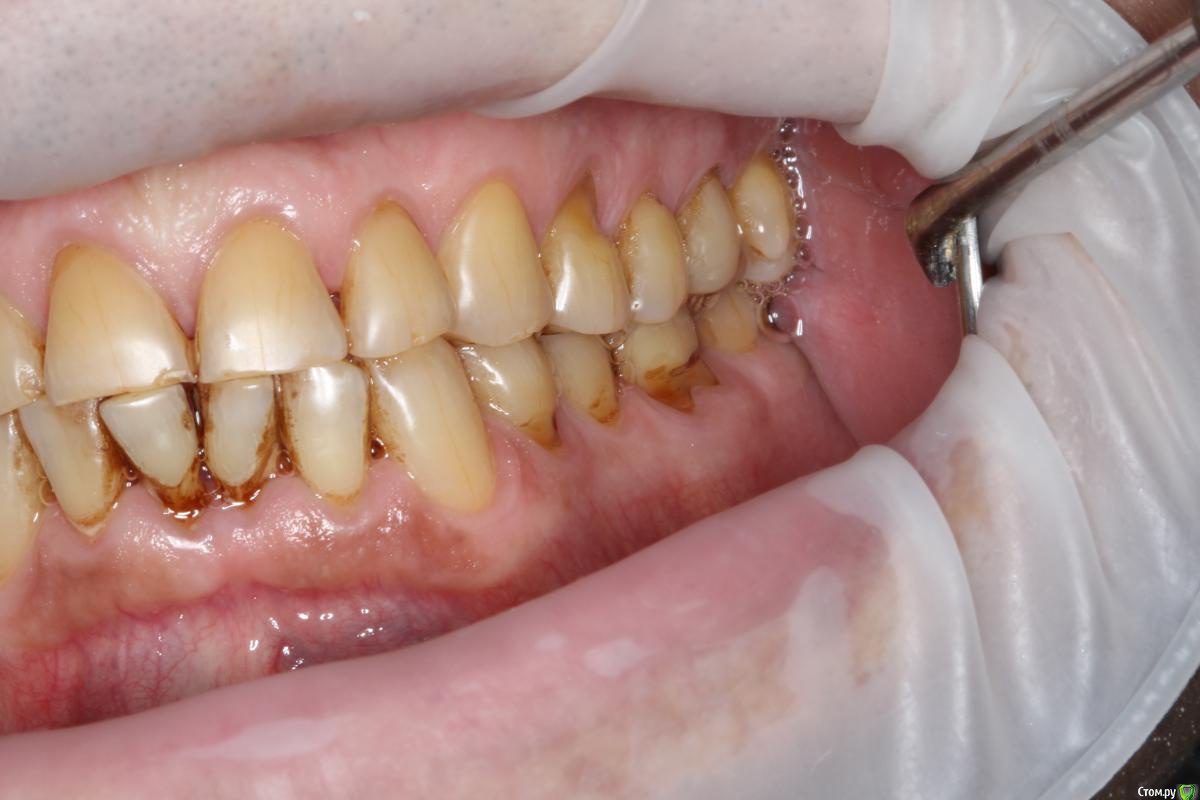

Robinbobin Опубликовано 27 марта, 2015 Поделиться Опубликовано 27 марта, 2015 (изменено) Пациент 57 лет с жалобами на стираемость зубов,чувствительность и бруксизм Хотелось бы услышать ваше мнение!!!! Изменено 27 марта, 2015 пользователем Robinbobin Ссылка на комментарий

Евгений Ходыкин Опубликовано 27 марта, 2015 Поделиться Опубликовано 27 марта, 2015 1) Стабилизировать пародонт.2) Закрытие рецессий, где это возможно.3) Вакс + мокап.4) Временный тотал.5) Постоянный тотал. 1 Ссылка на комментарий

Robinbobin Опубликовано 28 марта, 2015 Автор Поделиться Опубликовано 28 марта, 2015 а с чем к вам этот пациент пришел с какой проблемой?С жалобами на стираемость,чувствительность зубов!!! Ссылка на комментарий

Robinbobin Опубликовано 28 марта, 2015 Автор Поделиться Опубликовано 28 марта, 2015 сколы керамики тут обеспечены.. да и по эстетике, лучше уж цельнозолотые Дело в том что пациент отказывается точить зубы и мы решили сделать оклюзионные накладки из прессовонной керамики Ссылка на комментарий